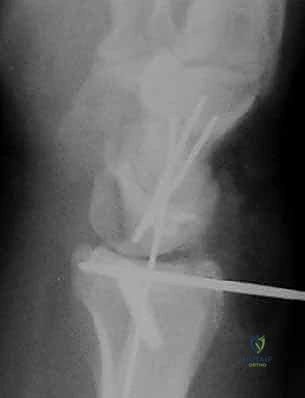

- كسور داخل المفصل (Intra-articular): الكسر يمتد ليشق السطح الغضروفي للمفصل (وهنا تبرز الأهمية القصوى لاستخدام المنظار).

الخطوة الرابعة: رد الكسر تحت الرؤية المباشرة

باستخدام أدوات دقيقة، يتم تحريك القطع العظمية المكسورة وإعادتها إلى مكانها الطبيعي. يراقب الجراح العملية عبر شاشة المنظار ليتأكد من أن السطح المفصلي أصبح مستوياً تماماً بنسبة 100%.

الخطوة الخامسة: التثبيت الداخلي

بمجرد استعادة الشكل التشريحي، يتم تثبيت العظام. قد يتم استخدام أسلاك كيرشنر (K-wires)، مسامير دقيقة، أو شريحة معدنية داعمة (Volar Plate) توضع من خلال شق صغير منفصل لضمان ثبات الكسر التام. يتم أيضاً خياطة أي تمزق في الأربطة إن وجد.